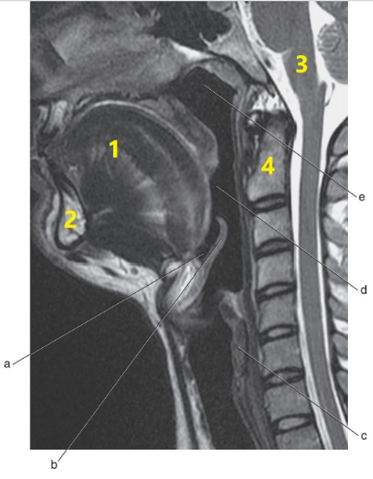

What is # 4 ?

C-1/C-2

What is # 1 ?

Tongue

What imaging plane is this ?

transverse

What anatomy is letter b ?

Epiglottis

Soft palate

What is # 3 ?

Brain stem